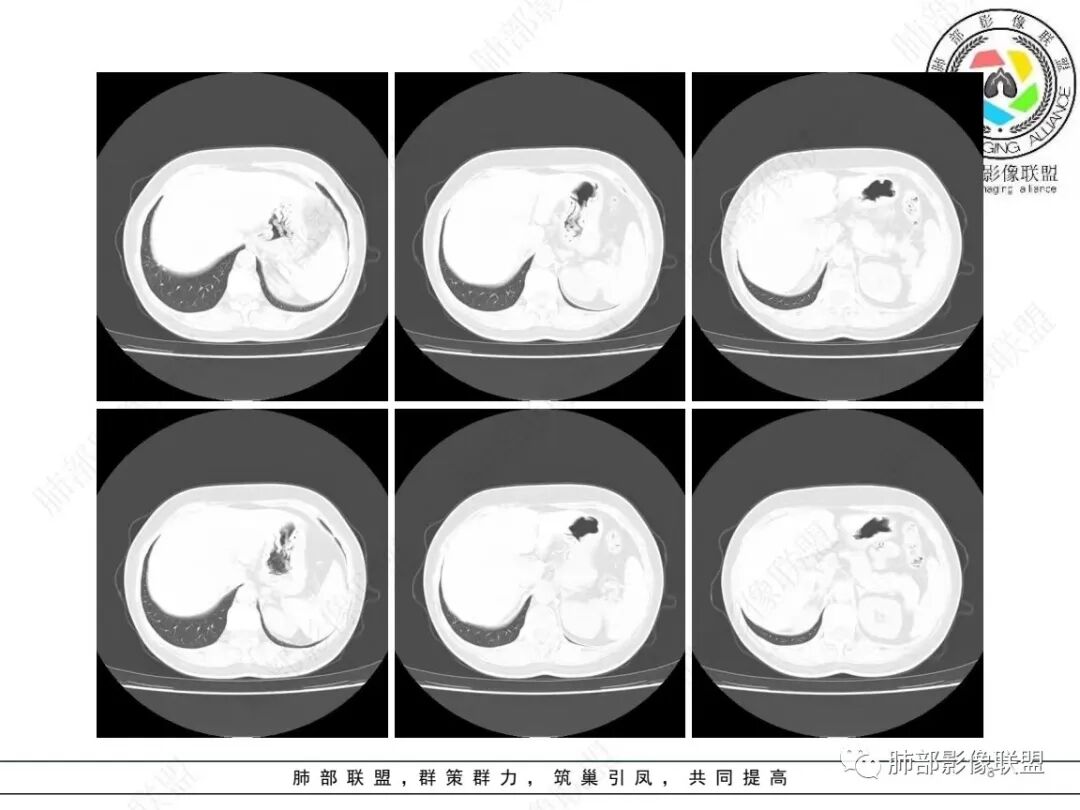

2、影像特点:右肺下叶胸膜下不规则结节,矢状位整体病灶沿着支气管方向呈斑片状,不均匀强化。病灶边缘多平直、凹陷(从部分层面可见极其像月牙铲),缺乏膨隆感,周围可见多发长索条影,病灶内可见多发充气支气管影,大部分支气管完全贯通病灶并轻度扩张,极少支气管进入病灶内堵塞,观察横断位视频、部分层面病灶周围可见边界欠清的ggo。纵隔窗病灶内未见明显钙化影。未见卫星病灶及树芽征。

3、综合分析:中老年女性胸膜下不规则结节,无特殊临床表现,实验室检查亦无特殊,病灶在部分断面呈斑片状,边缘多平直甚至凹陷,缺乏分叶及膨隆感,未见粗短毛刺及胸膜凹陷,部分层面似见”月牙铲“样外形,但缺乏张力的“月牙铲”不太可靠。灶周磨玻璃晕也会让人警惕肺腺癌可能,磨玻璃影边界是否清晰常须薄层仔细分辨。

实性密度为主结节影,支气管密切相关,边缘多平直,缺乏分叶膨隆感,缺乏张力,有磨玻璃晕但边界不清。更符合慢性炎性病变。

病理提示隐球菌感染可能。肺部隐球菌感染孤立性病灶与肺腺癌的鉴别诊断是个永恒的话题。